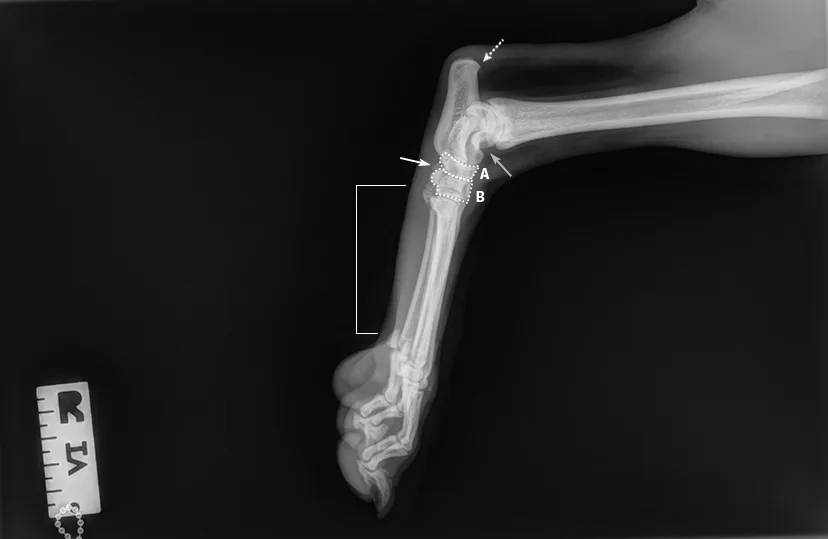

Author Insight

The trochlear ridges of the talus should be superimposed (gray arrow), and the calcaneus (dashed arrow) should not be foreshortened. The proximal (A) and distal (B) row of tarsal bones should align with clear superimposition, with visible joint space between the 2 rows of bones (white arrow). Perfect superimposition of the metatarsal bones (bracket) cannot occur because of the procurvatum of the foot. The dewclaw (if present) will lie caudally.